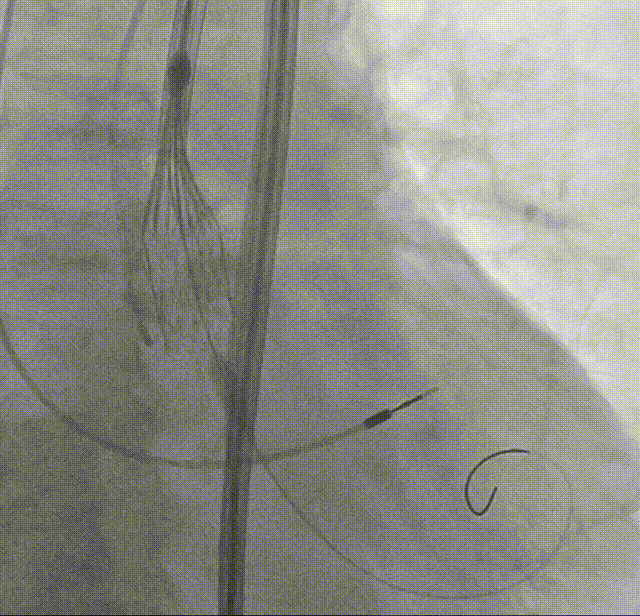

根部造影:可见开放受限,反流明显

AL1导管+直头导丝顺利跨瓣

导管测压:跨瓣压差高达120mmHg

18mm球囊预扩:可见无腰有漏,经评估决定装载TAVTF25瓣膜